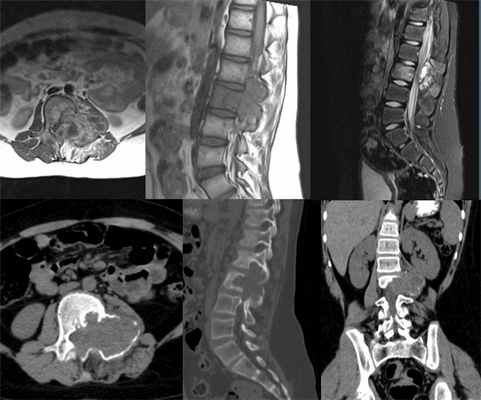

(Слева) Схема аксиального среза: показана аневризмальная костная киста, представляющая собой экспансивное мультикистозное объемное образование в заднем отделе тела и корней дуги позвонка, распространяющееся в эпидуральное пространство. Характерно наличие в полости кист уровней жидкости.

(Справа) Рентгенография в прямой проекции:аневризмальная костная киста Т12, характеризующаяся симптомом отсутствующего корня дуги. Краниальное и каудальное распространение опухоли определяется зоной костной деструкции, захватывающей тело позвонка, а также его дугу. (Слева) Аксиальный срез, Т2-ВИ: аневризмальная костная киста Т12, характеризующаяся наличием множественных уровней жидкости, образующихся вследствие оседания компонентов крови. Переходная зона с нормальной костью узкая и склерозированная. Видны признаки разрушения кортикальной пластинки, распространения опухоли в спинномозговой канал и сдавления спинного мозга.

(Справа) На сагиттальном Т2-ВИ у этого же пациента определяются признаки распространения опухоли в тело позвонка и спинномозговой канал. Важнейшим моментом дифференциальной диагностики является определение источника происхождения опухоли.